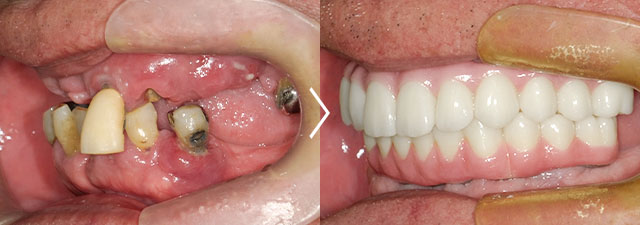

この患者様は上顎をすでにオールオン6で治療済みで、今回は下顎をオールオン6で治療しました。

オールオン6 セラミックタイプ ¥3,100,000(税抜)